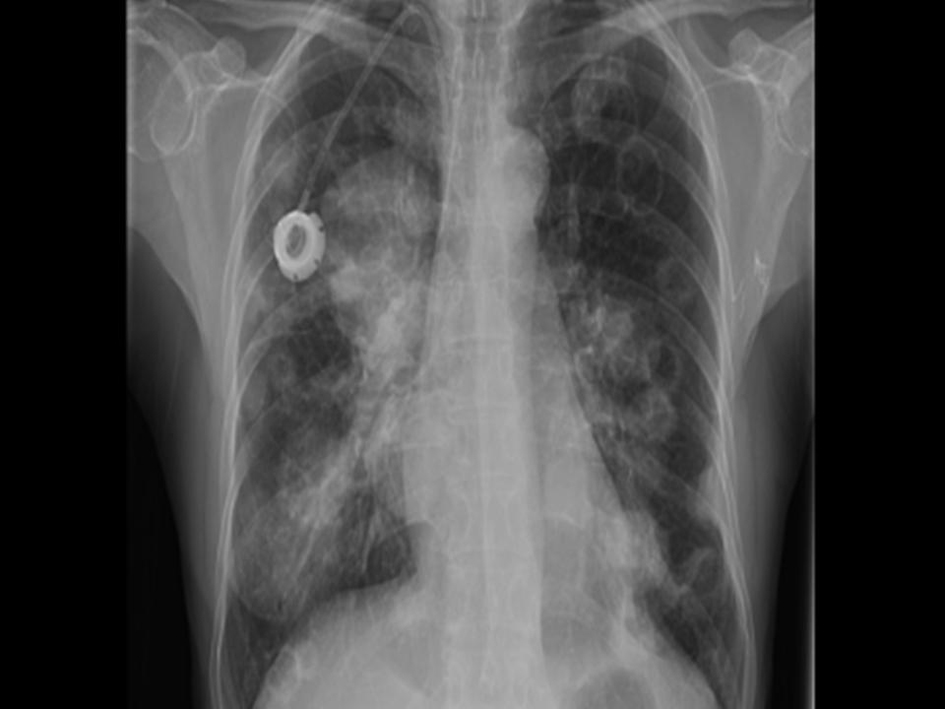

A previously healthy 62-year-old Asian American female presented at the City of Hope Cancer Center for evaluation of an enlarging breast lump and an accompanying BIRADS category 2 mammogram. Further radiologic studies, including MRI and ultrasound of the breast revealed a 3.5 cm × 3.5 cm × 2.3 cm mass, with no evidence of systemic metastases. Biopsy of the mass revealed the metaplastic breast cancer (MBC) with spindle cell features and with triple negative (estrogen, progesterone, and HER2/neu receptor negative) phenotype. She was started on neoadjuvant chemotherapy consisting of docetaxel 60 mg/m2 given intravenously on day 1, and leucovorin 500 mg/m2, cisplatin 25 mg/m2, and 5-fluorouracil 500 mg/m2 each infused over 24 hours for four days and to be repeated for 3 cycles. However, she progressed after one cycle. She underwent mastectomy with axillary node dissection with the final pathology revealing a T3 lesion and no evidence of lymph node diagnosis. She then received four cycles of adjuvant doxorubicin 60 mg/m2 and cyclophosphamide 600 mg/m2 and then started local-regional radiation therapy. However, after one week of radiation (1,800 cGy) she developed a fever, and complained of cough, shortness of breath, and fatigue. Chest X-ray revealed new multiple bilateral cavitary nodules and focal infiltrates in the lateral aspect of the right upper lobe (Fig. 1). The differential diagnosis included opportunistic, possible fungal infection, however metastatic disease could no be ruled out. On computerized tomography scan (CT) of the chest consolidation in the lateral right upper lobe measuring 4cm was seen, and, bilateral well-defined rounded lung nodules measuring up to 2.7 cm were described, with several of them demonstrating central cavitation. Multiple new small mediastinal nodes noted, measuring up to 1.1 cm in the pretracheal region. CT-guided biopsy was performed and confirmed the presence of clusters and pools of malignant singe cells present with spindle cell features that were morphologically compatible with the previously known MBC. Bronchial cultures were obtained and were negative for fungi and bacteria. She was started on capecitabine 1,250 mg/m2 twice daily orally on 2 weeks on, one week off schedule. After 2 weeks of capecitabine there was evidence of rapid progression and decline of her condition. The patient opted to discontinue treatment and received comfort measures only. She expired two months after being diagnosed with metastasis.

![]() Click for large image | Figure 1. Chest X-ray showing new multiple bilateral cavitary nodules and focal infiltrates in the lateral aspect of the right upper lobe. |